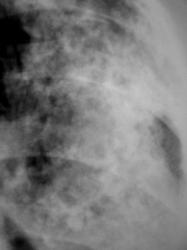

Иллюстрации 1, 2. Тотальное снижение прозрачности легочной ткани слева значительной интенсивности, неоднородной структуры. Средостение несколько смещено влево. Справа определяется компенсаторная эмфизема, слева умеренно выраженный плеврогенный цирроз.

Иллюстрации 3, 4. Фрагменты рентгенограмм с увеличением. Структура затемнения неоднородная, ноздреватая. На боне интенсивного затемнения визуализируются округлые участки просветления. Местами определяются более интенсивные участки затемнения известковой плотности в виде «очаговости».

Иллюстрации 7, 8. Структура затемнения неоднородная, имеет «ноздреватый» характер.